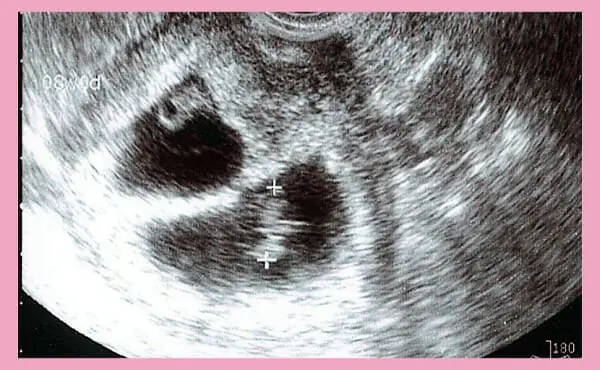

こちらの画像は、双子の8週目のエコー写真です。